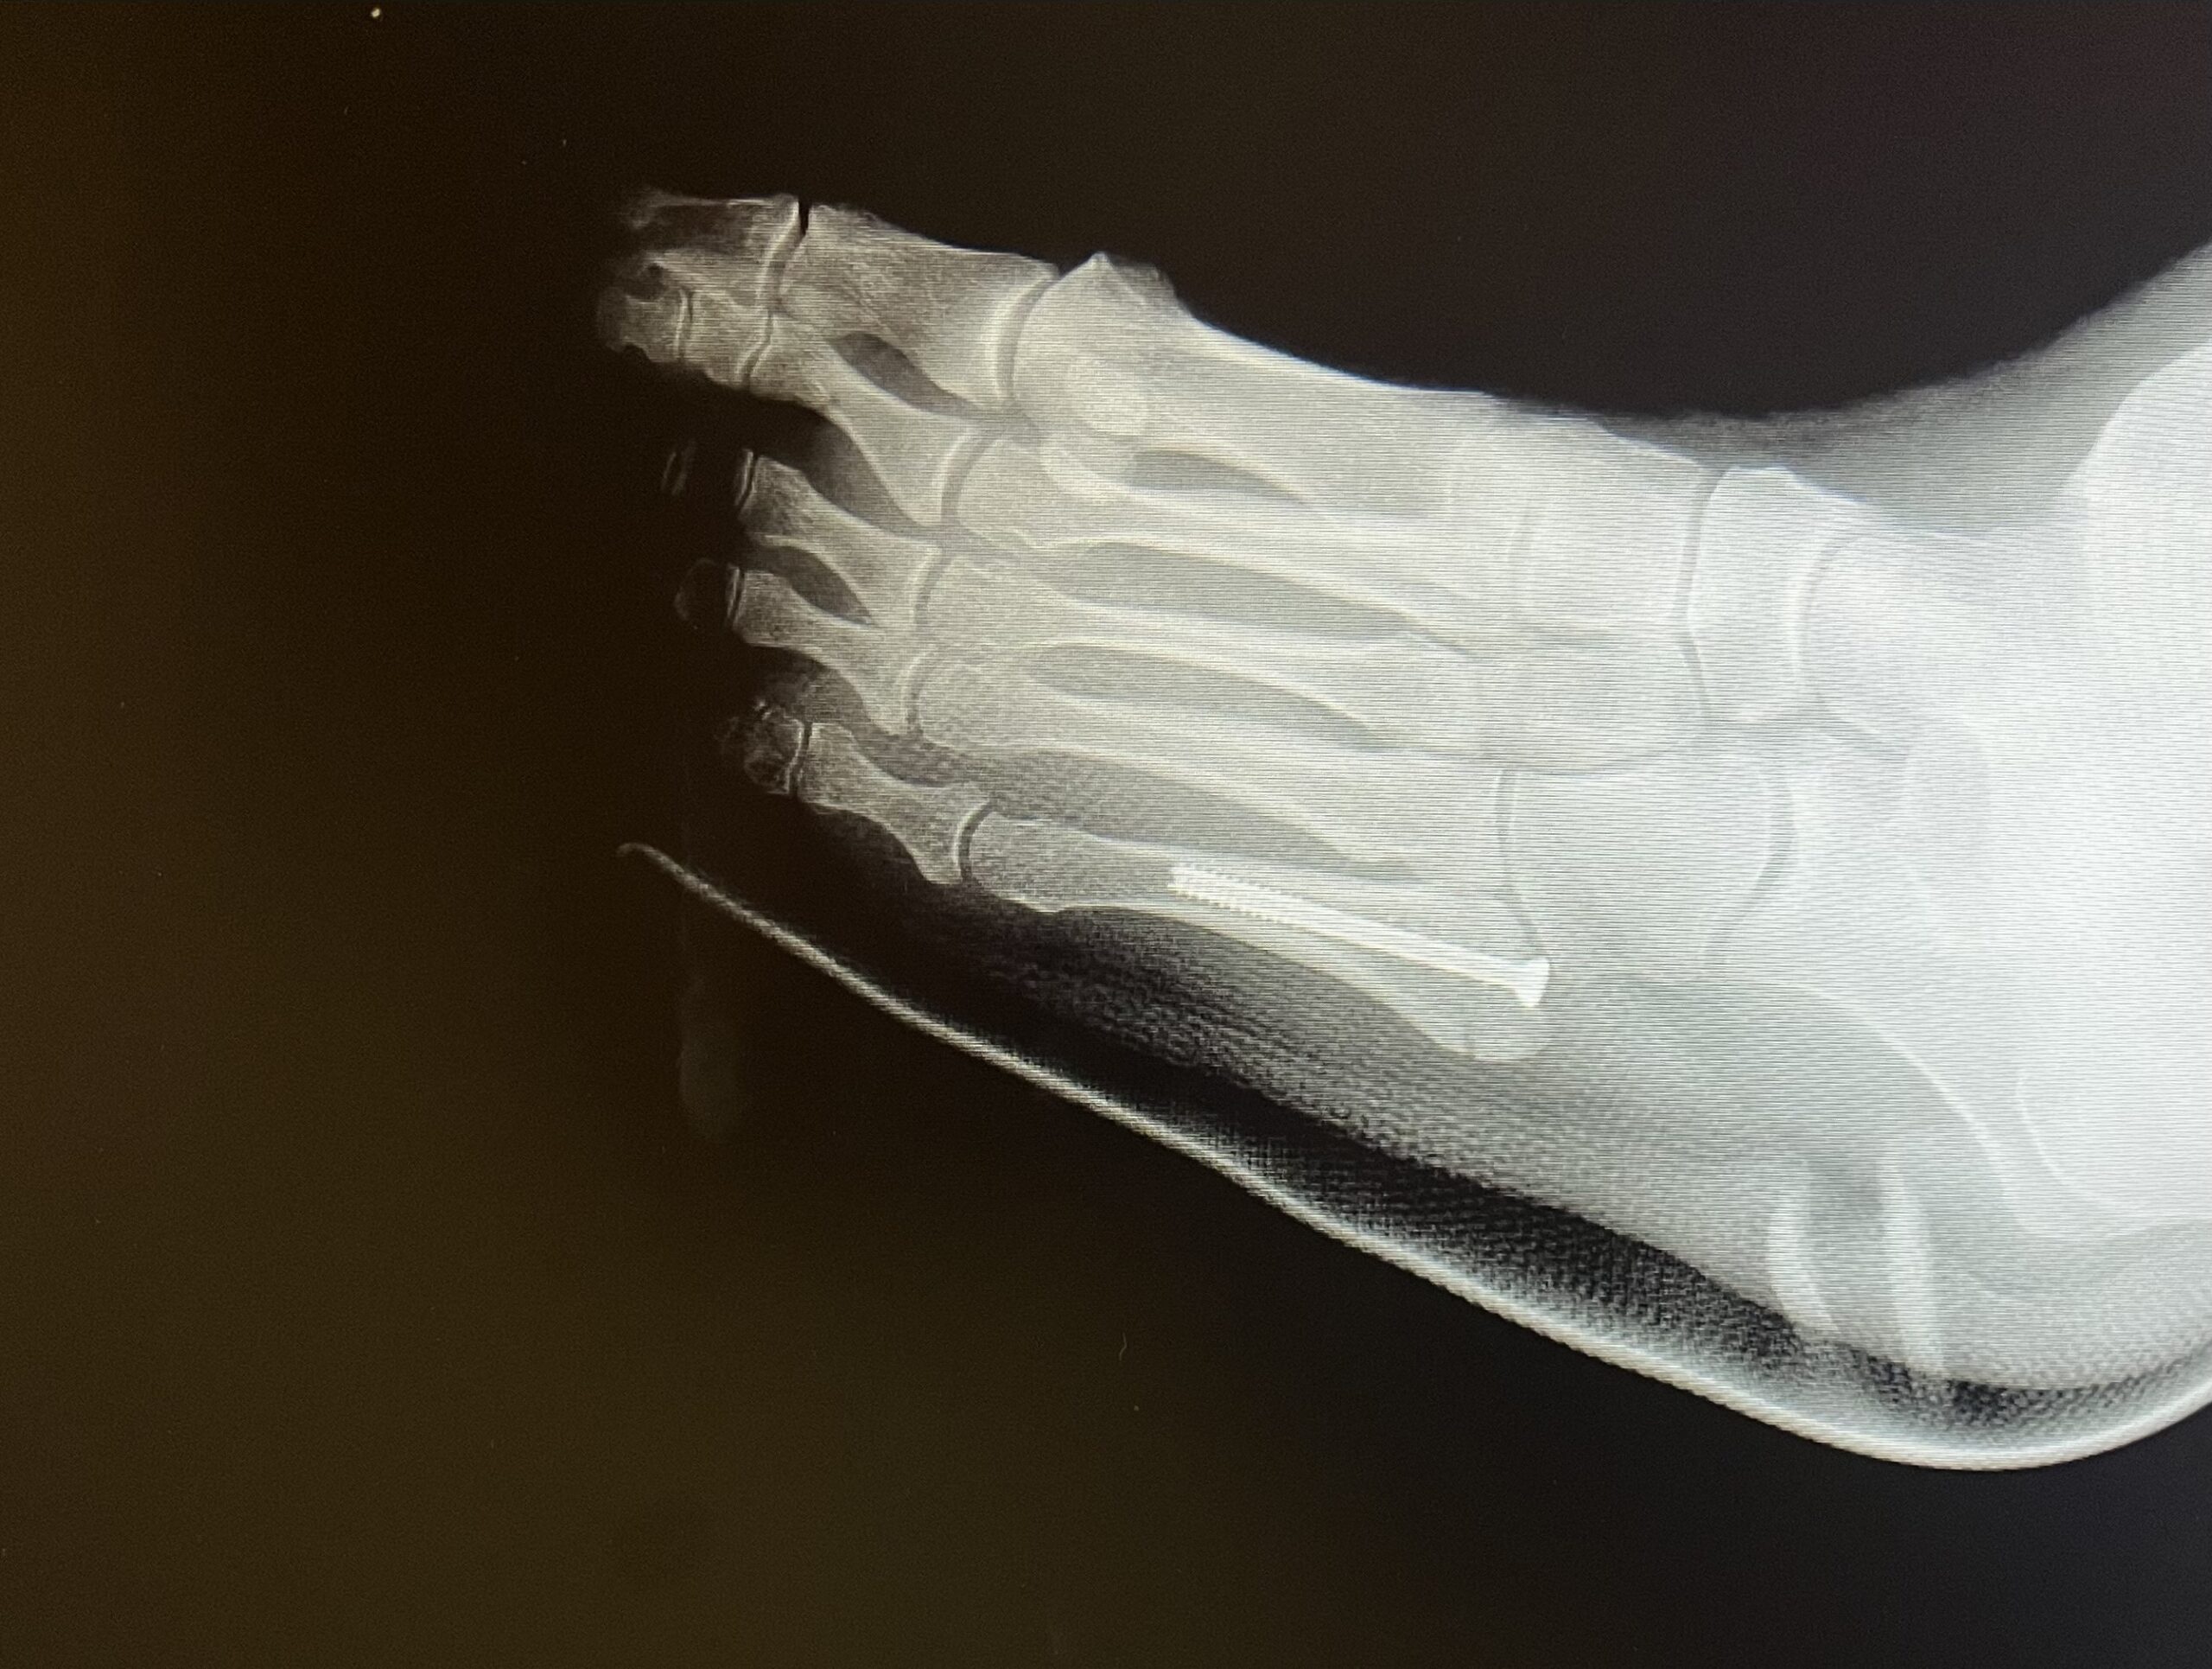

Η μέθοδος οστεοσύνθεσης ενός κατάγματος Jones συνίσταται στην τοποθέτηση ενός ενδομυελικού κοχλία, διαδερμικά. Η επάνοδος του ασθενούς στις καθημερινές και στις αθλητικές του δραστηριότητες επιτυγχάνεται στο μικρότερο χρονικό διάστημα.